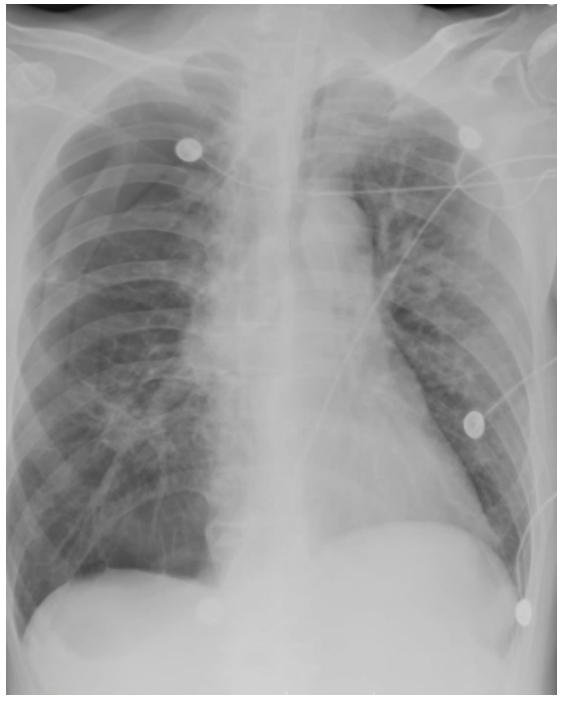

床旁支气管镜:隆突锐利,左右各叶支气管可见少量黏稠白色分泌物,予充分吸引,未见明显痰栓,各叶段予生理盐水肺泡灌洗,回收灌洗液(BALF),送检微生物培养。D-二聚体0.98 mg/L(胃内容物隐血阳性,预防性抗凝暂未实施,物理预防VTE)。考虑出现人机不协调可能是气道痉挛所致。调整呼吸机参数,更换为容量控制+压力支持模式,设定VT 为350 ml;加用阿曲库铵肌松;气道雾化治疗频率更换为q4h;甲泼尼龙剂量调整为40 mg q12h。调整后气道峰压下降至22 cmH2O。复查血气分析:pH 7.343,PaCO2 64.5 mmHg,PaO2 152 mmHg,氧合指数381 mmHg,乳酸1.5 mmol/L。患者呼气相延长好转,气促症状改善。2024年1月23日20:07,患者入院46 h,气促较前加重,哮鸣音明显,RASS评分-1分。复查血气分析:pH 7.206,PaCO2 104 mmHg,PaO2 59 mmHg,HCO3- 41.4 mmol/L,乳酸0.8 mmol/L。复查胸片:未见右侧新发气胸,左侧气胸未见进一步吸收,炎症不明显(图3)。予加深镇静镇痛。调整呼吸机参数为SIMV+PSV。1月23日22:04血气分析:pH 7.276,PaCO2 86.8 mmHg,PaO2 71.7 mmHg,HCO3- 40.4 mmol/L,乳酸1.3 mmol/L。1月24日09:34血气分析:pH 7.335,PaCO2 80 mmHg,PaO2 67.7 mmHg,HCO3- 40.1 mmol/L,乳酸1.3 mmol/L。(1)患者二氧化碳潴留反复加重的原因是什么?气道痉挛缓解困难的原因是什么?(2)并发气胸加重?——复查胸片可以排除这种可能。(3)并发肺栓塞?——D-二聚体基本正常,临床表现也无明显证据。1月24日BALF培养结果提示为烟曲霉。是否是致病菌?该患者危险因素符合:①慢性病基础(慢阻肺);②糖皮质激素应用史;③广谱抗生素应用史。不符合之处:①体温正常;②炎症指标正常;③胸部影像学未见新发感染征象;④外周血G试验/GM试验正常。1月24日加用伏立康唑片剂0.2 g q12h鼻饲,复查胃内容物隐血阴性,VTE评分5分(高危),根据体重调整剂量后加用依诺肝素3000 U预防性抗凝治疗。甲泼尼龙减量至40 mg qd,雾化减至q12h。继续有创呼吸机辅助通气,动态调整呼吸机参数,镇静镇痛,肌松。完善lgE、过敏原检测;动态复查胸片、血气分析、炎症指标。检查结果回示:IgE 37 lU/ml;吸入物+食入物过敏原阴性。1月26日复查血常规+hs-CRP:WBC 6.4×109/L,NEU% 92.0%,EOS% 0.0%,Hb 124 g/L,PLT 201×109/L,hs-CRP 9.24 mg/L。呼吸机参数:SIMV+PSV, PCV/PSV 20 cmH2O, PEEP 10 cmH2O, VT 200~500 ml。1月25日血气分析:pH 7.402,PaCO2 70.1 mmHg,PaO2 94.4 mmHg,氧合指数270 mmHg,乳酸1.1 mmol/L。1月26日血气分析:pH 7.431,PaCO2 67.7 mmHg,PaO2 80.5 mmHg,氧合指数230 mmHg,乳酸1.4 mmol/L。1月27日血气分析:pH 7.462,PaCO2 60.8 mmHg,PaO2 88.2 mmHg,氧合指数252 mmHg,乳酸1.6 mmol/L。1月27日复查胸片:与1月24日胸片对比,气胸未进一步加重,亦未见新发感染病灶(图4)。患者气道痉挛仍然存在,1月27日试停肌松后气道痉挛加重,人机不协调,脱机困难,1月29日出现发热(图5),气道内分泌物未见增多。抗感染药物已经覆盖了烟曲霉,患者为何出现发热症状——口服伏立康唑血药浓度不足?合并其他微生物感染?出现脓毒血症?寻找依据:查伏立康唑血药浓度为5.26 μg/ml(正常范围)。1月29日复查血常规:WBC 6.7×109/L,NEU% 89.3%,EOS% 0.0%,Hb 127 g/L,PLT 260×109/L,hs-CRP 3.66 mg/L。PCT、IL-6均正常,完善血培养【5~7天,等待结果】。经验性加强抗感染,停用哌拉西林他唑巴坦,更换为美罗培南。BALF送检NGS进一步明确致病菌。1月31日复查胸片:没有明显的新发感染迹象(图6)。送检BALF NGS 1天后结果回报:烟曲霉(序列数2272),乙型流感病毒(序列数47)。伏立康唑改为针剂0.2 g q12h,联合卡泊芬净50 mg qd(首剂70 mg),联合两性霉素B脂质体50 mg biw雾化;加用玛巴洛沙韦抗病毒。患者气道痉挛明显,气胸风险大,床边备胸膜切开包。复查血常规+hs-CRP:WBC 7.8×109/L,NEU% 86.6%,Hb 130 g/L,PLT 198×109/L,hs-CRP 1.0 mg/L。血培养回报阴性(双瓶双侧)【脓毒血症依据不足】。经过上述治疗,患者体温较前下降,支气管镜下气道分泌物较前减少,气道痉挛部分缓解,呼吸机参数改善,试停肌松。1月31日血气分析:pH 7.423,PaCO2 59.9 mmHg,PaO2 75 mmHg。2月1日血气分析:pH 7.420,PaCO2 58.6 mmHg,PaO2 81.2 mmHg。2月4日患者再次出现发热,体温最高38.1℃,气道痉挛加重,血气分析提示二氧化碳潴留加重,PaCO2 71.6 mmHg。复查炎症指标:WBC 12.2×109/L,NEU% 93.2%,hs-CRP 32.97 mg/L,PCT 0.068 ng/ml,IL-6 19.8 pg/ml。复查胸片提示两肺炎症改变,右肺下野团片影(图7)。复查BALF细菌培养:纹带棒状杆菌>103CFU/ml。真菌培养:无真菌生长。复测伏立康唑血药浓度3.03 μg/ml。纹带棒状杆菌是定植,还是致病?2月4日复查胸部CT:与入院时CT相比,出现两下肺斑片渗出影(图8)。考虑患者合并细菌感染。